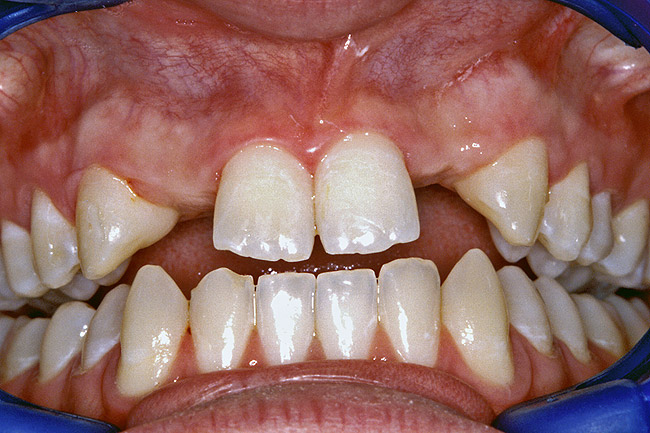

A 17-year-old boy presented with a history of congenitally missing maxillary lateral incisors. The patient had been under the care of an orthodontist for several years to manage his occlusion during his adolescent growth phase. The patient originally presented with his parents after being told that the “braces were ready to be removed, and their son was now ready for implants to replace the missing teeth.” This is not an u.common circumstance, and unfortunately the orthodontic alignment was performed before the patient was sent to the restoring dentist. Therefore, the orthodontist was not aware of the space requirements for future implant placement. This case highlights the importance of proper.communication between all members of the implant team, especially during the orthodontic planning phase. The patient’s medical history was unremarkable, and the patient was found to be healthy and a good potential candidate for dental implants to replace the missing lateral incisors.

Periapical radiographs were taken to help determine the mesial-distal inclinations of the adjacent tooth roots (Figure 1). The radiographs revealed a serious issue, convergent roots for the right canine and right central, which eliminated that area as a potential implant-receptor site. The space between the left central and canine teeth was minimal, although the roots were relatively parallel. Clinical examination (manual palpation of the root eminences superiorly to the vestibule on the right side) confirmed the root convergence (Figure 2A). The flat, wide zone of the keratinized tissue and lack of interdental papilla was evident for the missing right lateral incisor. There was a marked difference in clinical appearance for the left lateral, which could impact the eventual plan of treatment (Figure 2B). Other significant clinical findings included bilateral facial bone concavities, which existed as a result of the congenitally missing tooth roots. As a diagnostic cue to the underlying bone topography, it is important to follow the demarcation between attached and unattached gingival tissue, and note the crestal width of the available keratinized tissue (Figure 2C).

Figure 2a  Pretreatment buccal views showed (A) root convergence, (B) a difference in clinical appearance of the left lateral, and (C) significant crestal width of keratinized tissue.

Figure 2a

Figure 2b  Pretreatment buccal views showed (A) root convergence, (B) a difference in clinical appearance of the left lateral, and (C) significant crestal width of keratinized tissue.

Figure 2b